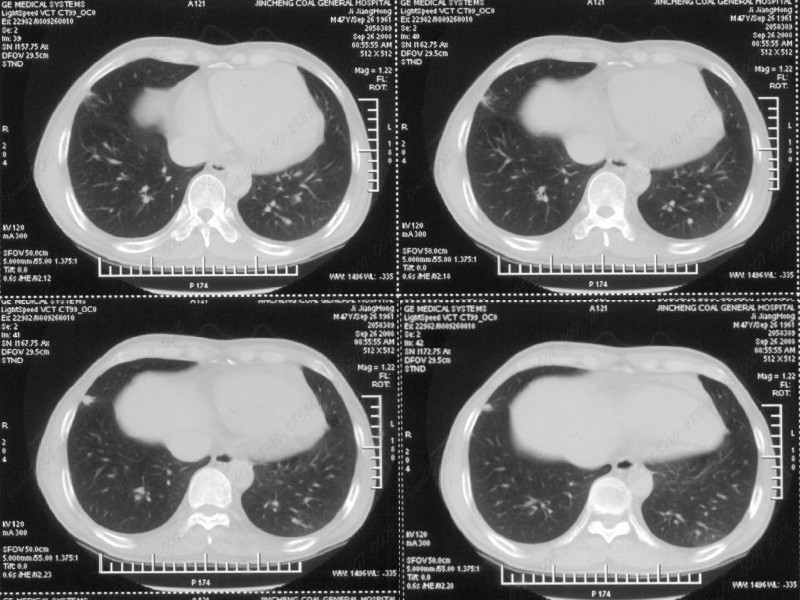

男性,47岁。胸部不适一年,ct检查发现右胸膜下结节。http://www.radida.com/bbs/forum.php?mod=viewthread&tid=46094

图像很清,资料很全。工作做的很细,向您学习!观阁下的强化图像发现,您们强化后扫描时间挺早,延迟时间大约在16—18秒之间吧。估计目的是为了观察肺动脉及分支的情况。但现有的资料并不能提示动脉栓塞改变。建议楼主可在机器上仔细观察,或许会有异常发现。另外,个人感觉右侧应为肺内结节而非胸膜结节。考虑肺内良性小结节,炎性假瘤可能性大。

病灶周围似有纤维化征像,增强明显强化,但中央可见点状低强化区,考虑慢性病变可能如炎性假瘤等,病灶边缘部分毛糙有切迹,双侧胸腔少量积液影,不除外恶性

结节未见明显强化,局部胸膜增后粘连,内缘纹理影增重伴小围星灶,局部胸膜下小三角状实变影,尖端见纤维索牵扯征,综合考虑炎性病变,有增殖表现,不出外tb灶

右肺中叶外侧段胸膜下结节状病灶,性质待定(不排除周围型肺癌可能)。

小结节的周围似乎与斜裂的走行有关,边缘分界不很清楚,与侧胸膜关系密切,有轻度强化,不能除外恶性,建议密切观察。

右肺静脉充盈缺损,左心房体积小,右肺动脉远端动脉充盈缺损,右肺血管影细小,考虑;右肺动脉远端栓塞.